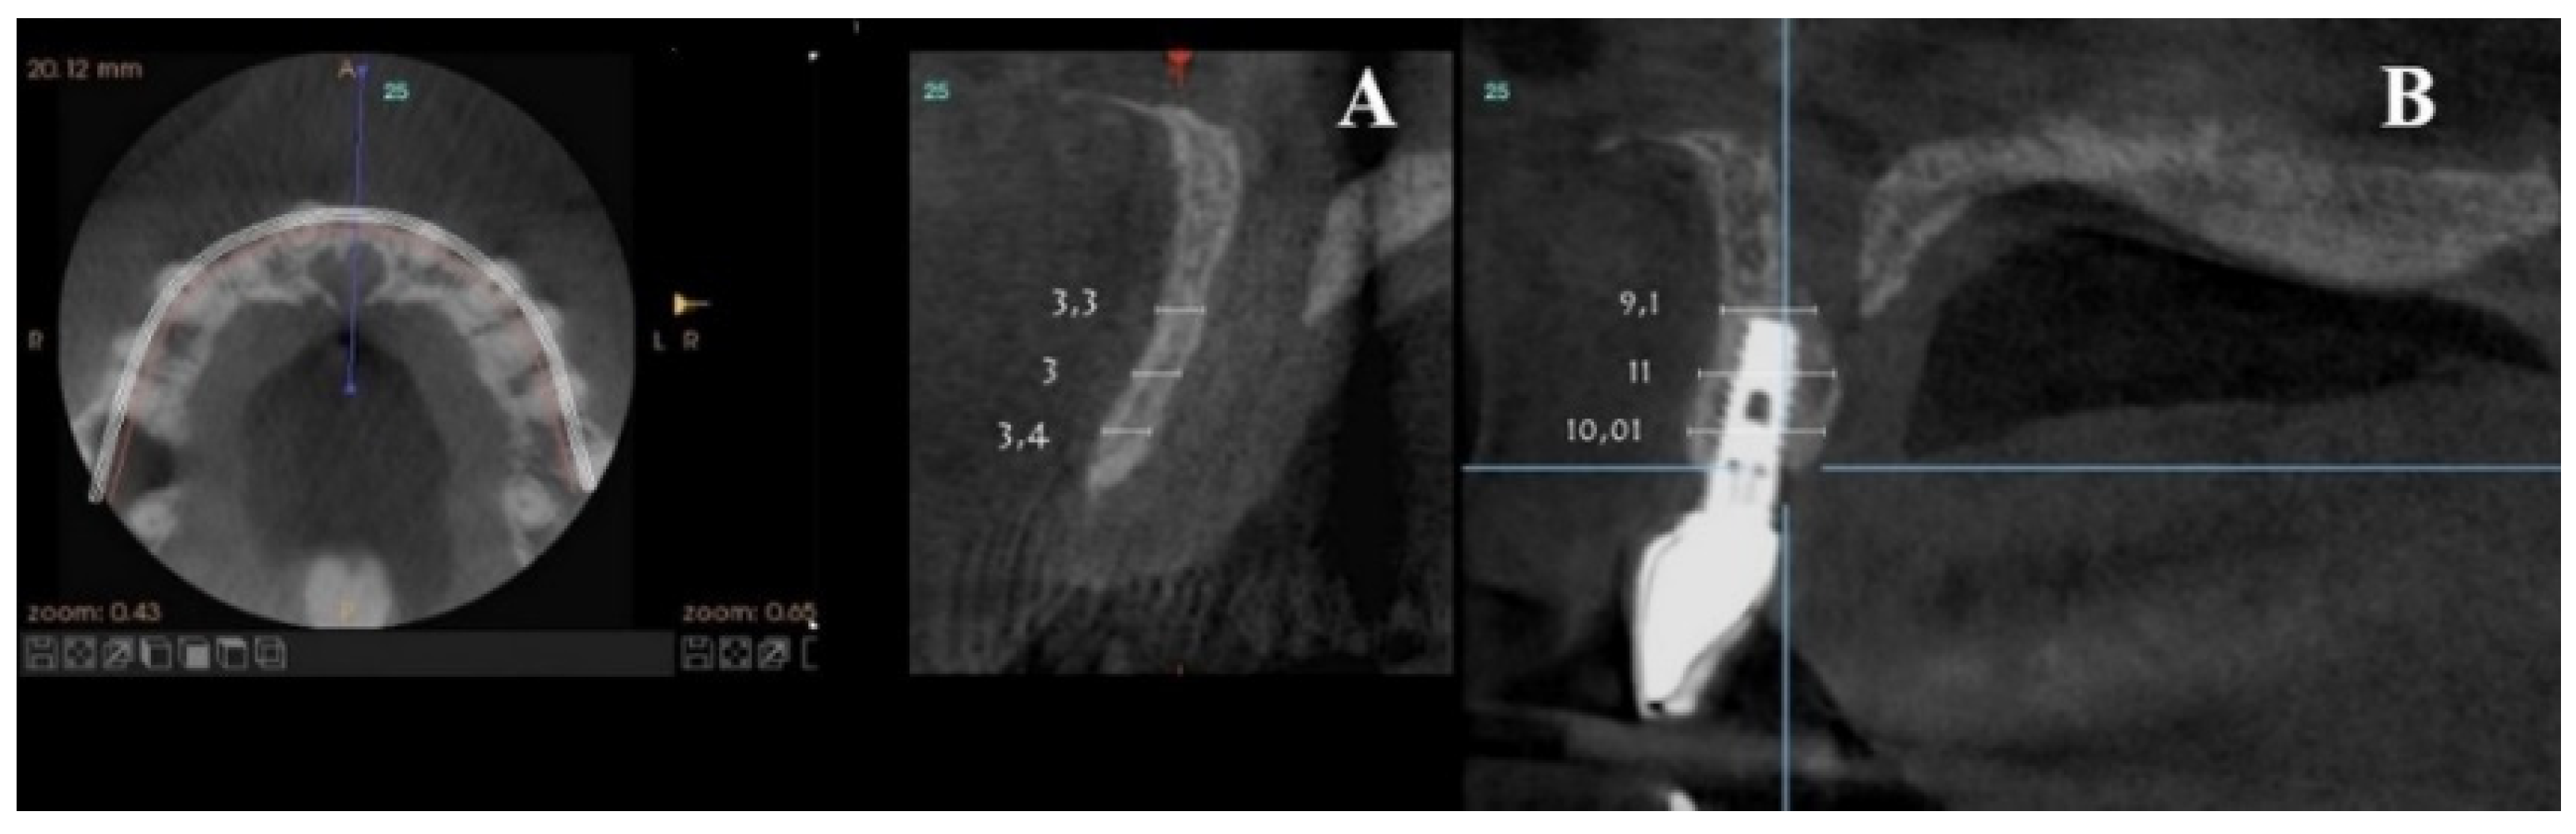

Axial sections corresponding to the middle part of the NPC showed the collapse of the vestibular plate and revealed the conduit’s size. All the cases presented thinning of the palatal ridge due to marked widening of the incisive foramen (Figure 2); so, according to the SAC Classification (i.e., simple, advanced, or complex), they were categorized as complex [2]. In addition, careful consideration had to be given to the nasopalatine bundle for correct three-dimensional positioning of the implant. Since the vertical and horizontal defects demanded bone augmentation before implant placement [17], a diagnostic wax-up was performed to determine the amount of bone needed in each case.

Figure 2.

Representative sections of a Cone Beam Computed Tomography (CBCT) scan in which the bone thickness of the maxillofacial region and the widening of the incisive foramen are observed. (A) Occlusal view. (B) Sagittal view.

For each patient, pre- and post-treatment CBCT measurements of the anterior ridge thickness of the aforementioned foramen were taken at different heights, i.e., 4, 8, and 14 mm apical to the marginal bone ridge. CBTC was performed at 90 Kv and 10 mA, with an 18-second exposure cycle on a Promax-3D plus equipment (Planmeca, Finland). The obtained images were analyzed with Romexis 4.4.0.R. A field of view of 40 mm by 50 mm was used, with an isoropic voxel size of 75 µm (0.075 mm). Serial slices (0.5 mm in thickness) with 0.5 mm reconstruction intervals were analyzed.

For the scanning procedure, the occlusal planes were oriented parallel to the horizontal plane. Medical imaging recording protocols were used for comparative measurements. First, image relationships were determined following the process of superimposition of tomographic images obtained by CBCT by using the Canny edge detection module of MATLAB R2018a (64-bit). Overlays were made in the areas of interest, obtaining identical reference points as those provided by the Canny filter.

For each patient, pre-surgical measurements were taken in the vestibular table observed from the sagittal plane, from the vestibular cortex to the anterior cortical wall of the NPC. In the same fashion, the vestibulo–palatine width was measured between 6.5 and 9.5 months (7 months on average) after implant activation.

Pre-surgical vestibulo–palatine width (mean ± standard deviation) of the anterior ridge at different heights (4, 8, and 14 mm apical to the marginal bone ridge) was 3.5 ± 2.0 mm; 5.4 ± 1.5 mm, and 6.1 ± 1.9 mm, respectively. Post-treatment total vestibulo–palatine width was 10.1 ± 2.0 mm, 10.5 ± 1 mm, and 13.4 ± 3.0 mm, respectively (Table 4).